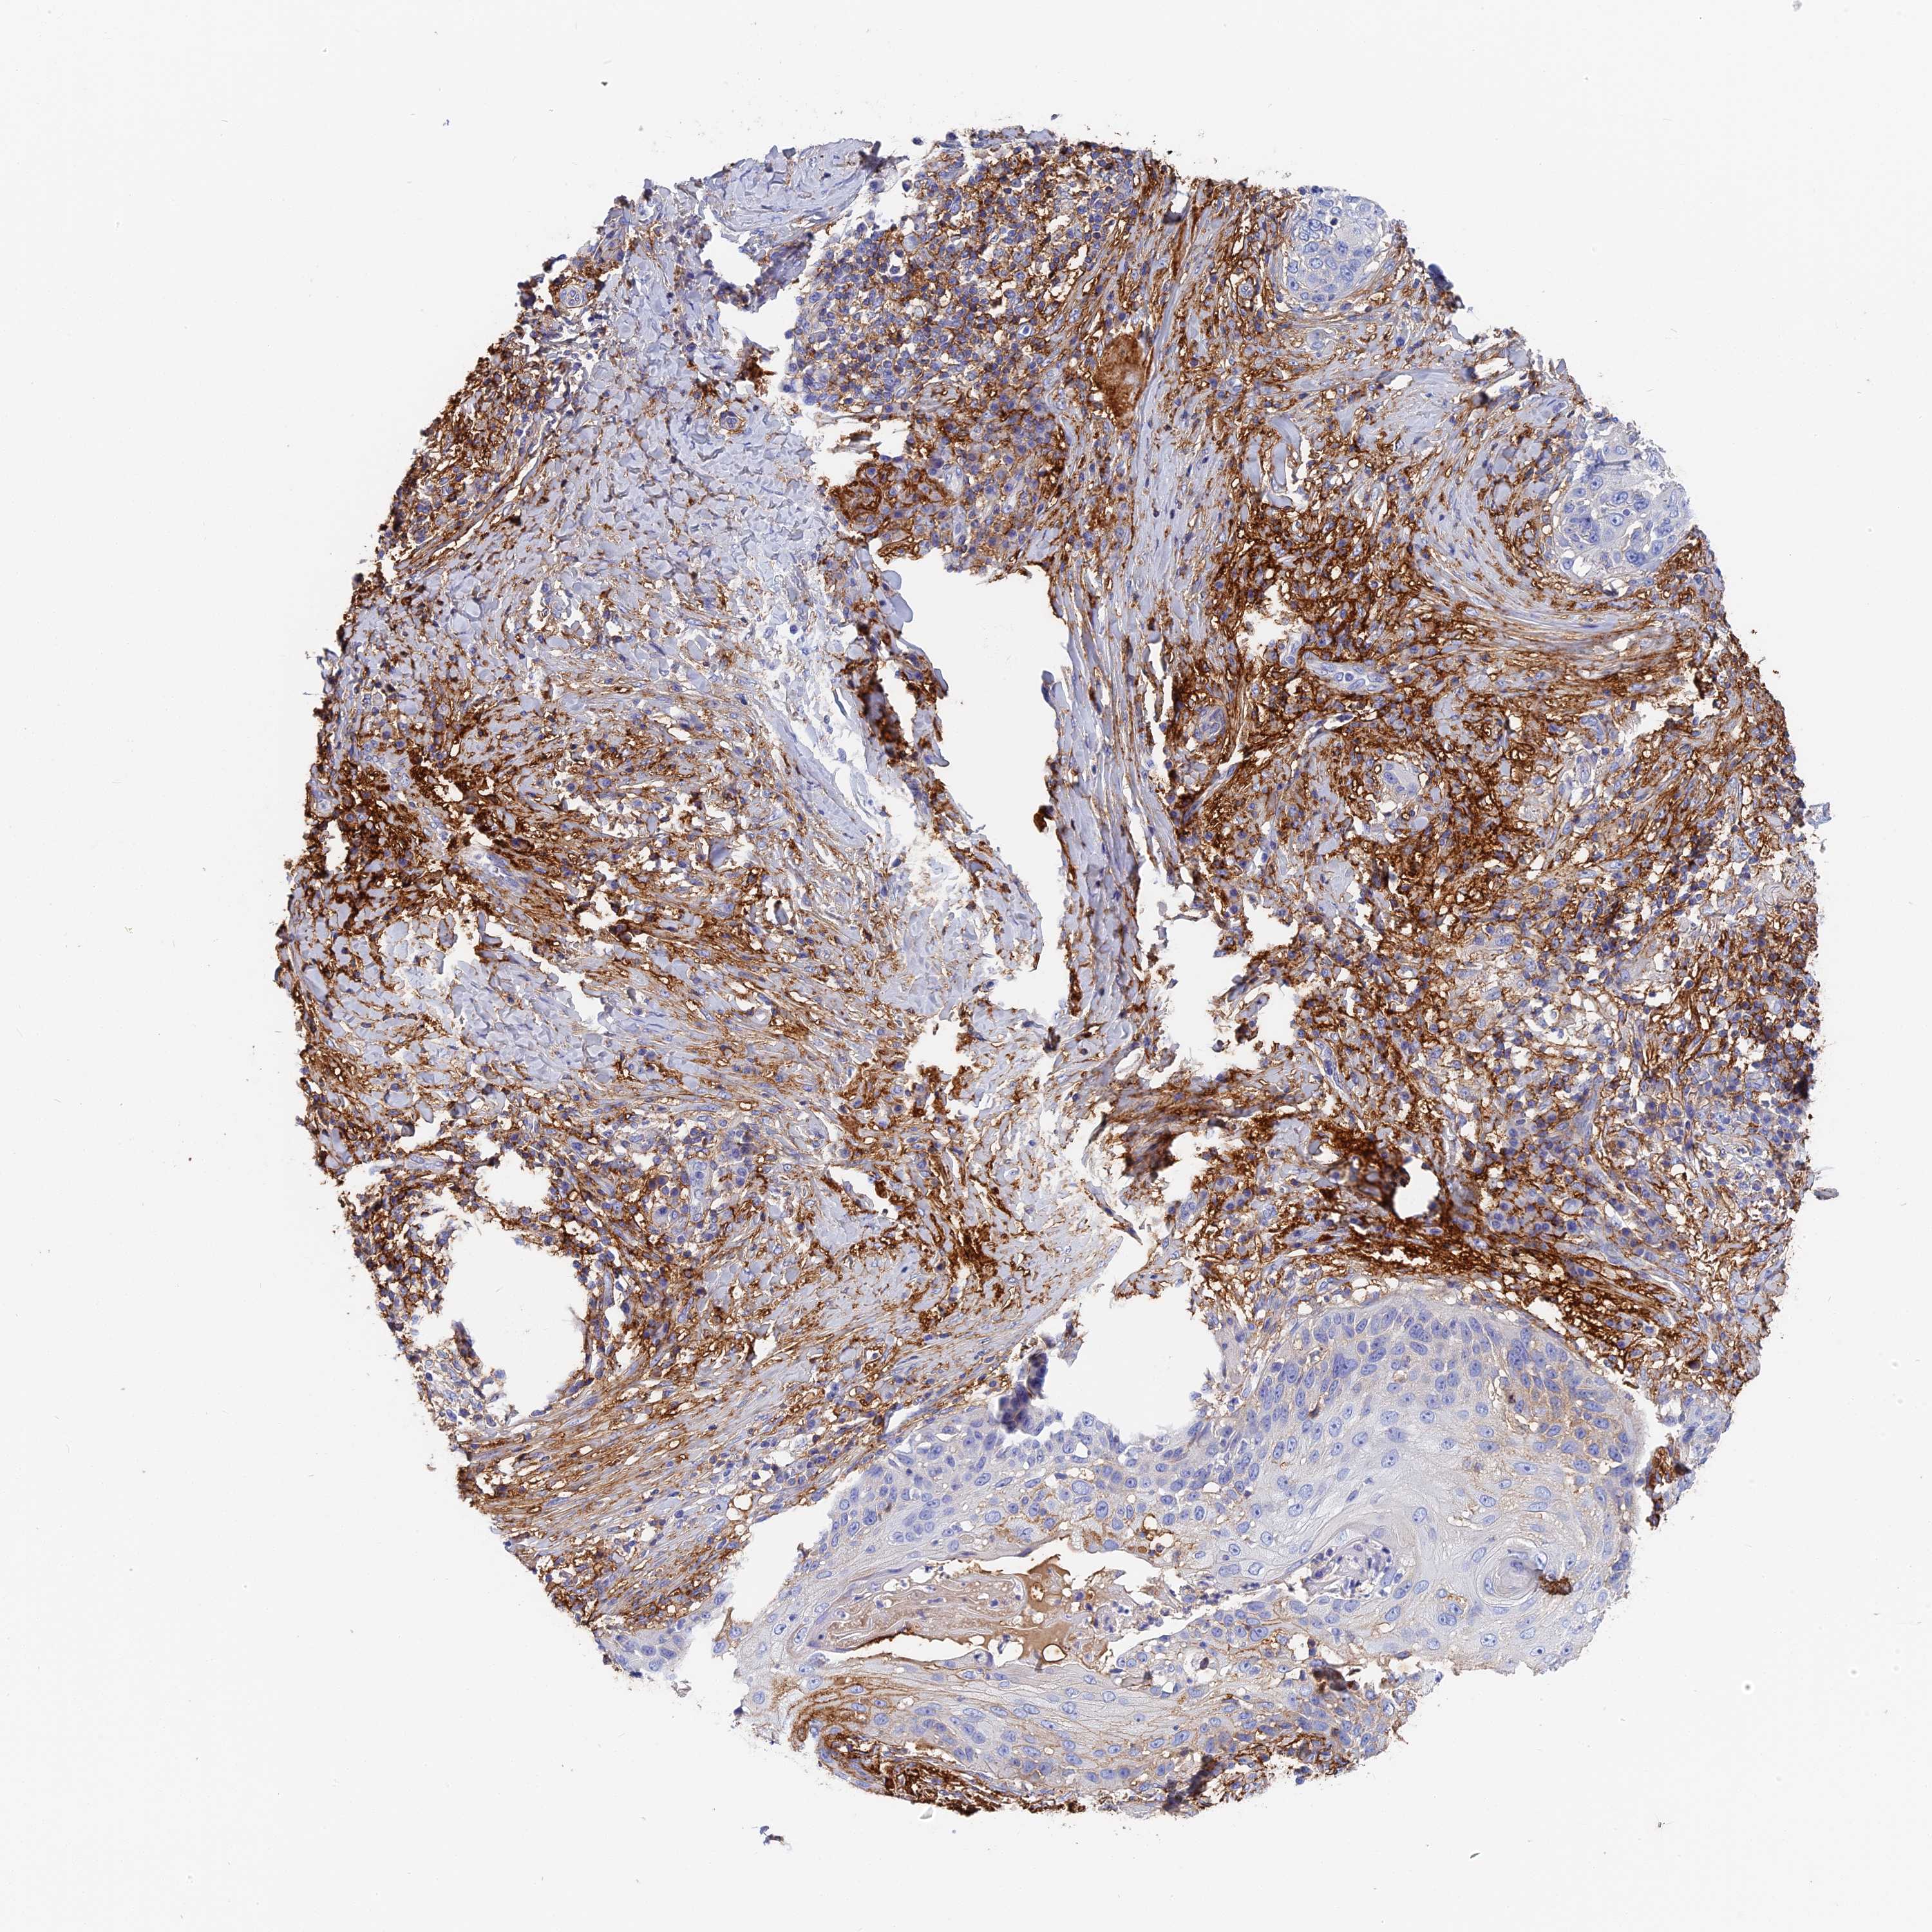

SKIN CANCER - Protein expressioni

A mouse-over function shows sample information and annotation data. Click on an image to view it in a full screen mode. Samples can be filtered based on level of antibody staining by selecting one or several of the following categories: high, medium, low and not detected. The assay and annotation is described here.

Antibody stainingi

Antibody staining in the annotated cell types in the current human tissue is reported as not detected, low, medium, or high, based on conventional immunohistochemistry profiling in selected tissues. This score is based on the combination of the staining intensity and fraction of stained cells.

Each image is clickable and will lead to virtual microscopy that enables deeper exploration of all samples and also displays staining intensity scores, fraction scores and subcellular localization as well as patient and tissue information for each sample.

Antibody HPA041639

Antibody HPA042049

Squamous cell carcinoma, NOS

Squamous cell carcinoma, metastatic, NOS